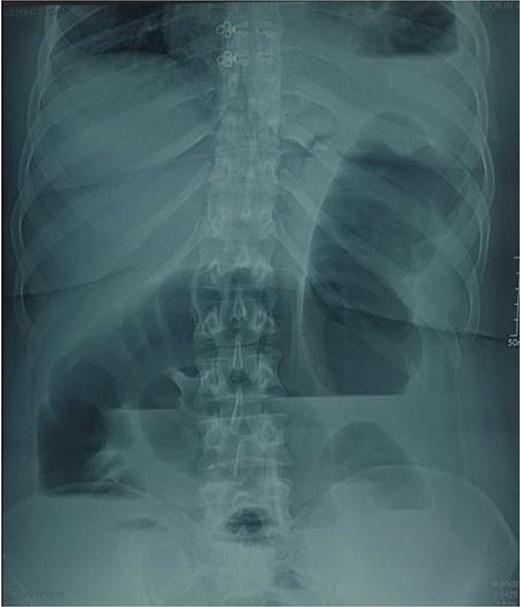

A 29-year-old female, with a history of cesarean section performed three months prior and no history of thoracoabdominal trauma, was admitted to the emergency department for an occlusive syndrome characterized by complete cessation of bowel movements and flatus, associated with vomiting, without other digestive or respiratory symptoms. On examination, the patient was conscious, haemodynamically and respiratorily stable. Abdominal examination revealed marked distension with epigastric tenderness, and digital rectal examination demonstrated an empty rectal ampulla. An initial plain abdominal radiograph, performed in the standing position and focused on the diaphragmatic domes, demonstrated colonic and small bowel distension with multiple air–fluid levels (Fig. 1). Subsequently, a thoraco-abdominopelvic CT angiography was performed, revealing a 3 cm left colonic herniation into the thoracic cavity through a partial posterolateral diaphragmatic rupture, associated with moderate left-sided pleural effusion (Figs 2–4). The herniation caused colonic stenosis at the diaphragmatic defect, with upstream distension of small bowel loops, the stomach remaining in its anatomical position (Fig. 5). These findings were consistent with acute intestinal obstruction secondary to a left-sided diaphragmatic hernia. Surgical management consisted of reduction of the herniated contents, assessment of their viability, and closure of the diaphragmatic defect using interrupted nylon sutures (sizes 2/0 and 0) (Fig. 6). Double drainage was instituted: a 28 Fr posteroinferior thoracic drain inserted through a dependent incision in the 5th intercostal space, and a Jackson–Pratt abdominal drain placed in the rectouterine pouch (Douglas’ pouch).

Image of an unprepared abdomen in a standing position, centered on the diaphragmatic domes, showing colonic and small bowel distension with air-fluid levels.